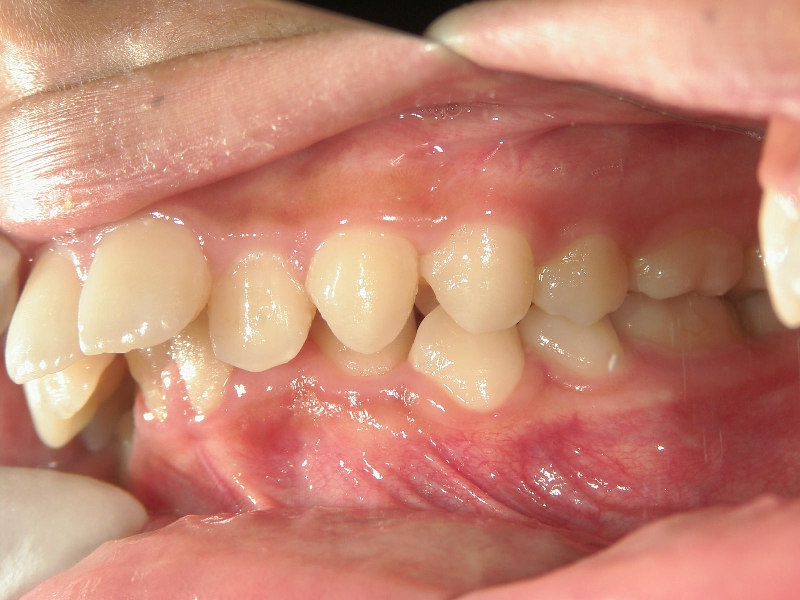

矯正歯科 治療後矯正歯科 全顎ワイヤー矯正 治療後矯正歯科(全顎ワイヤー矯正)治療後

矯正歯科 治療後

no.18_2196_治療後_右.jpgno.18_2196_治療後_正面.jpgno.18_2196_治療後_左.jpg